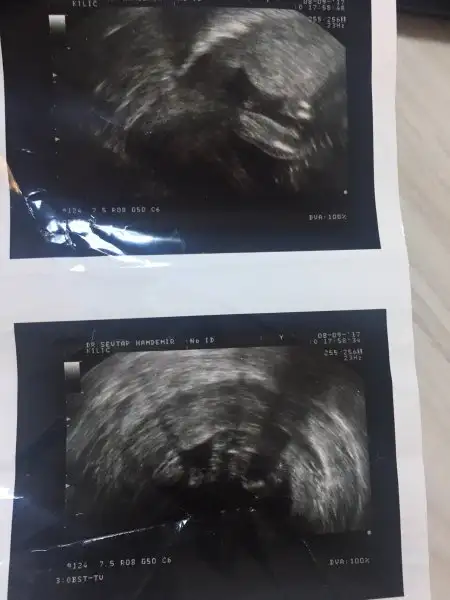

kızlar alttan baktıgı ultrason bu neredesınde yazıyor bu rahım agzı uzunlugu bı bakar mısınız

Eklentiler

• IMG_4783.webp

IMG_4783.webp

7,5 KB · Görüntüleme: 61

• IMG_4784.webp

IMG_4784.webp

13,2 KB · Görüntüleme: 74

• IMG_4785.webp

IMG_4785.webp

9,9 KB · Görüntüleme: 80